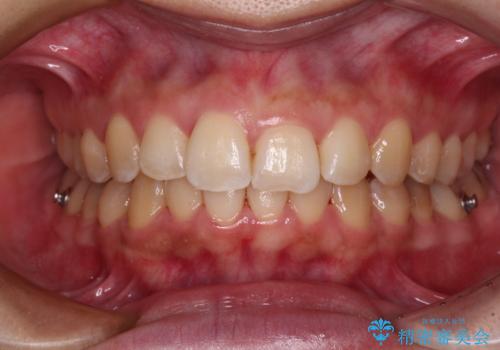

前歯のデコボコをインビザライン矯正で綺麗に改善

- 上下前歯のデコボコを気にして来院された患者様です。

全体的に叢生は軽度であったため、インビザラインにて矯正治療を行うこととしました。

舌の突出癖改善がうまくいかず、途中で舌小帯の切除を行いました。

気になる段差を納得いくまで改善させたため、治療期間は長くなりましたが、綺麗な仕上がりとなりました。